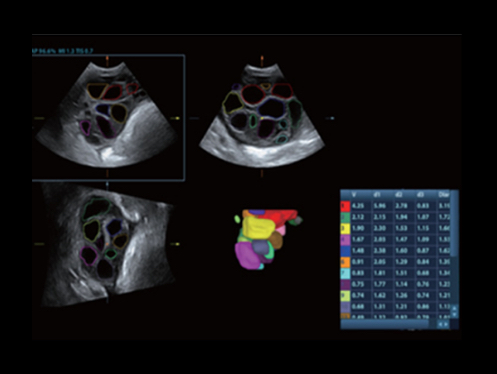

ImĂĄgenes clĂnicas